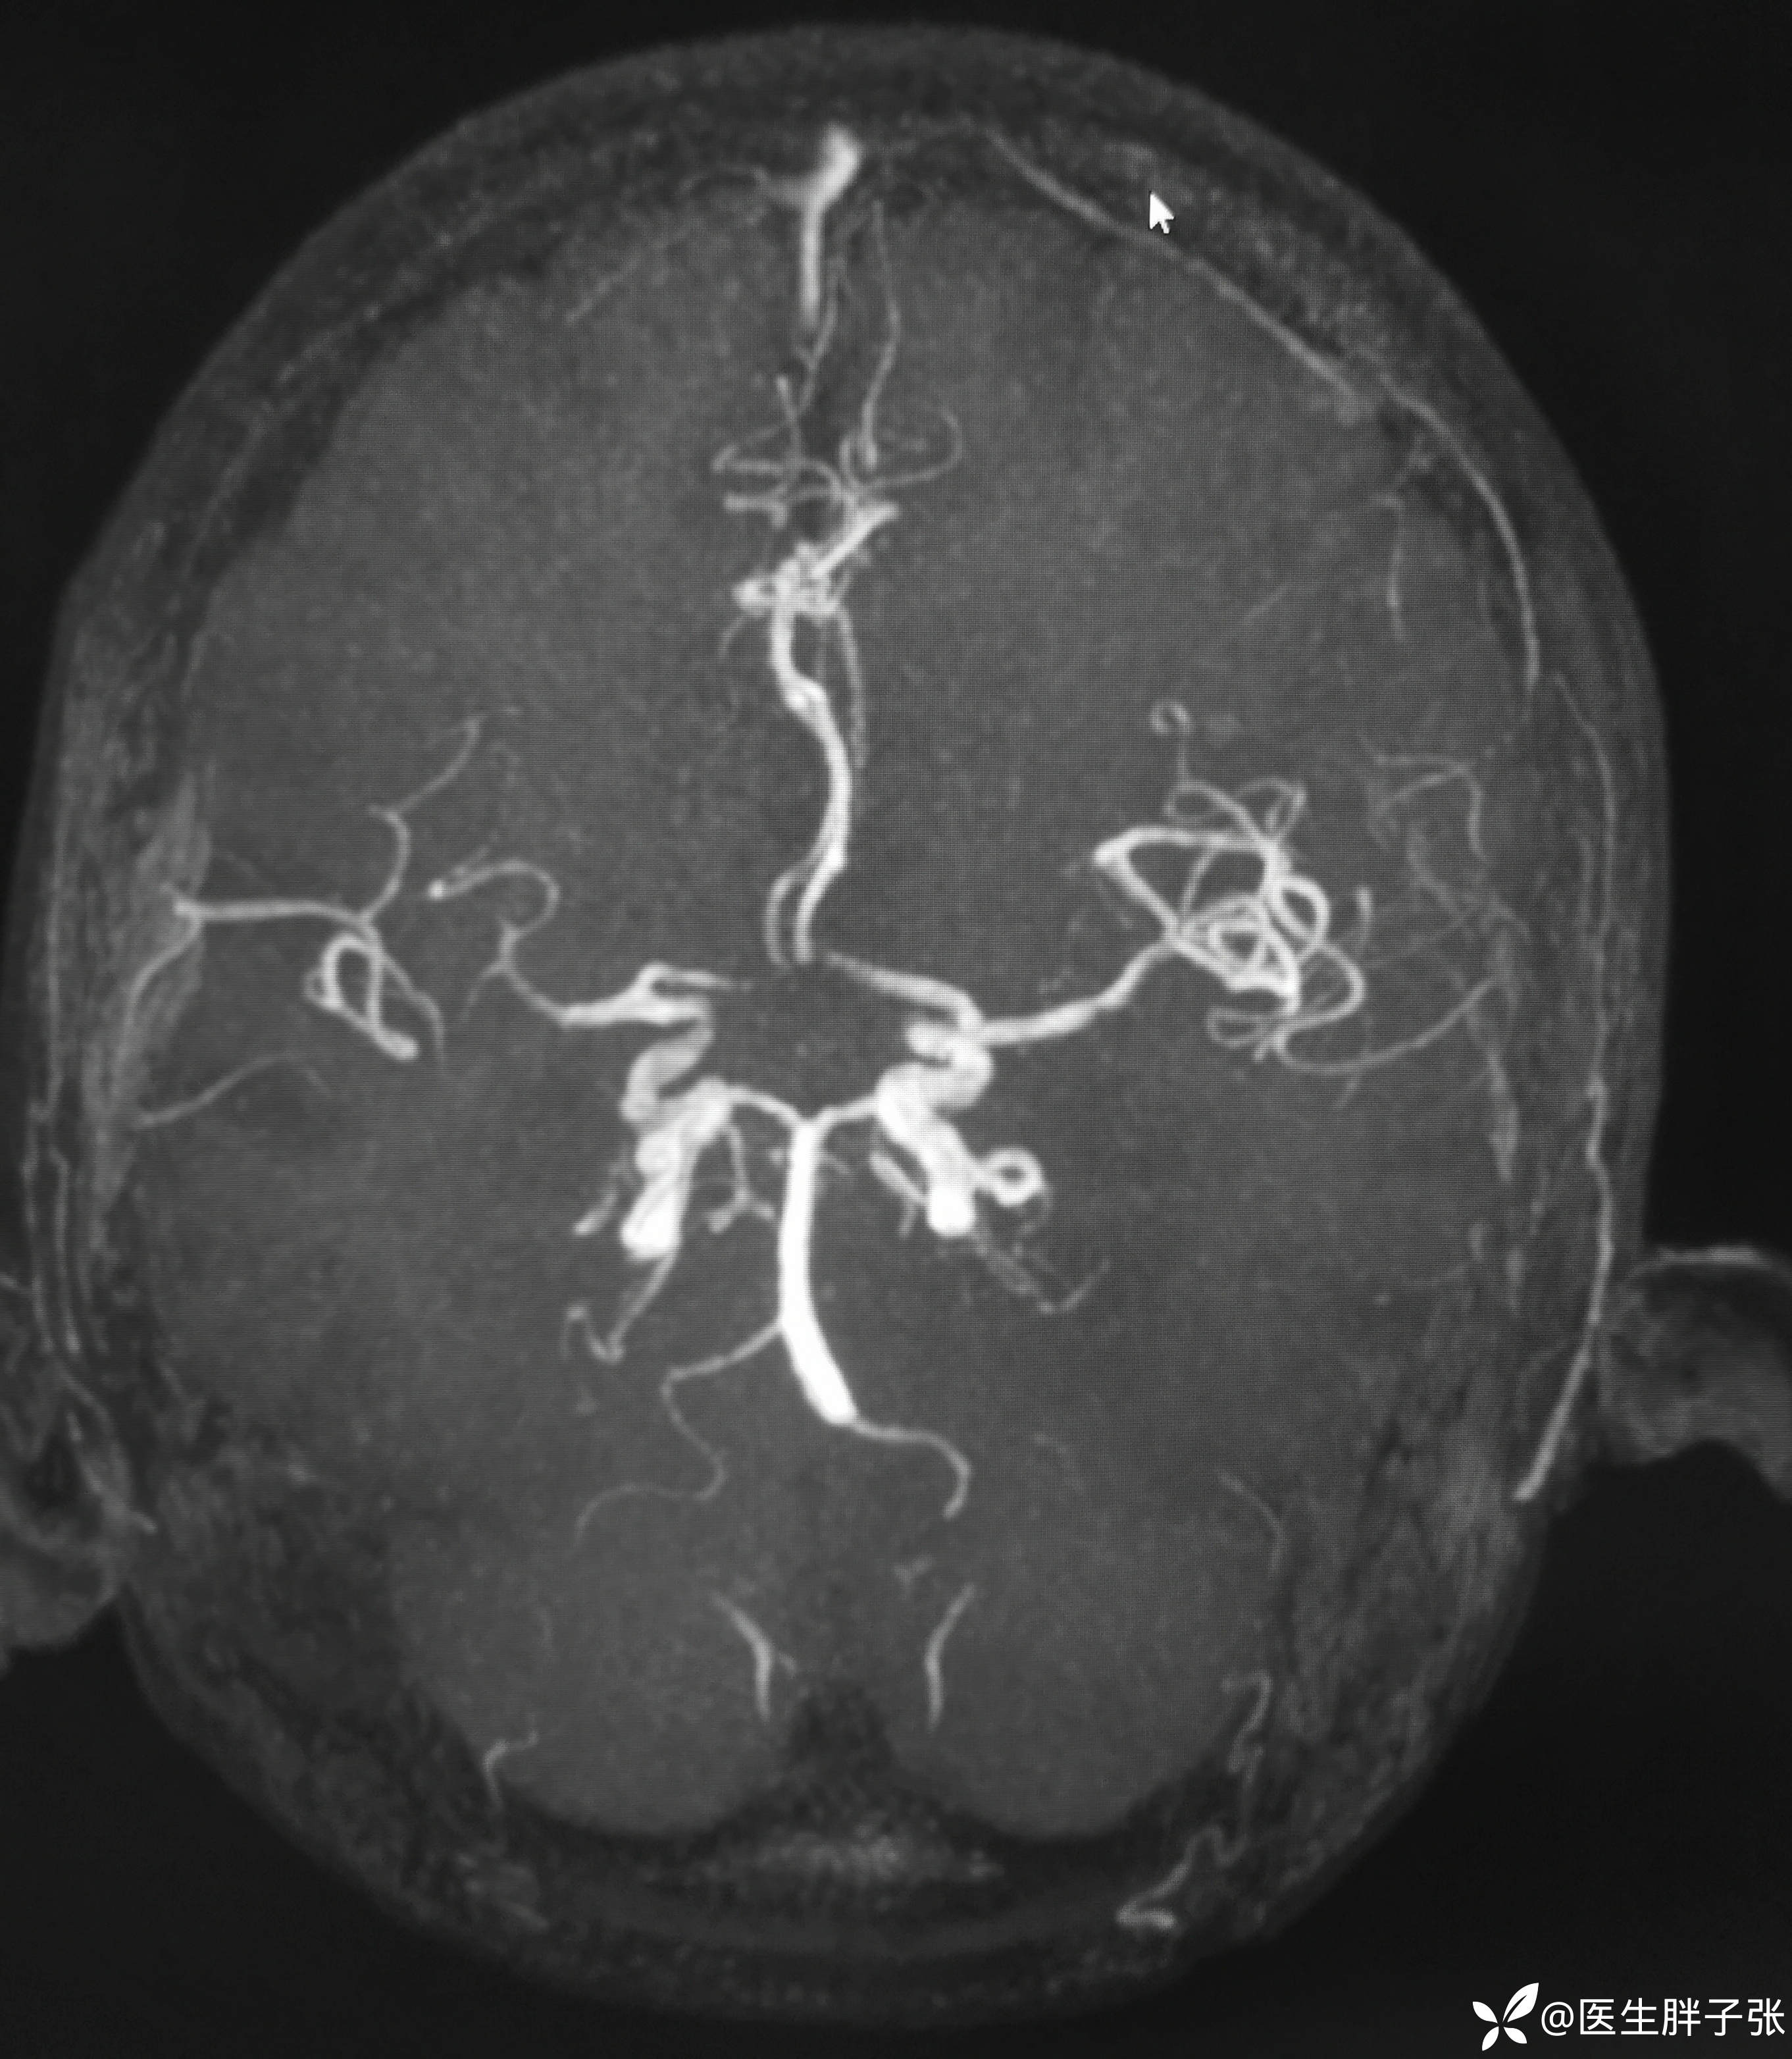

颅脑MR:右侧颞叶新近梗死灶;老年性脑改变;右侧大脑中动脉部分M2段及以远未见显示,建议头颈部CTA检查。

溶栓过程顺利,无并发症。患者发病前有腹泻,MRA提示右侧大脑中M2闭塞可能